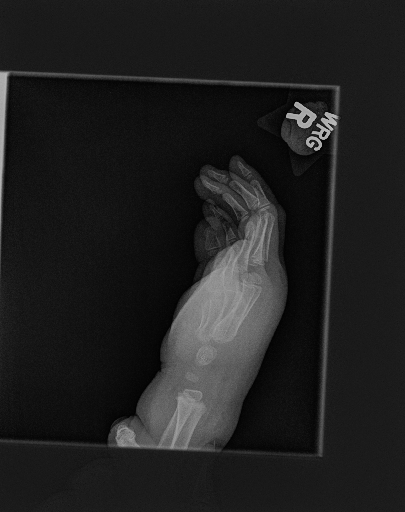

In this work, we focus on a subset of the MURA dataset [17] containing only hand images. In total, we have 5,543 images of 2,018 studies of 1,945 patients. Each study is labeled as negative or positive, where positive means that there was an anomaly diagnosed in this study. There are 521 positive studies, with a total of 1,484 images. Figure 1 shows some examples from the dataset. In summary, our contributions are as follows:

The first step in our pipeline is to detect the X-ray image carrier in the image. To this end, we apply OpenCV’s contour detection using Otsu binarization [14], and retrieve the minimum size bounding box, which does not need to be axis-aligned. This works sufficiently well as long as the majority of the image carrier is within the image (cf. Figure 3). However, the approach might fail for heavily tilted images or those where larger parts of the image carrier reach beyond the image border.

Hand Localization

To further improve the detection of hands, and in particular split the images where two hands are depicted on one image, we manually labeled approximately 150 bounding boxes in the images. Using this small dataset, we fine-tune a pre-trained single shot multibox detector (SSD) [12] with MobileNet as taken from TensorFlow. An exemplary results can be seen in Figure 3.